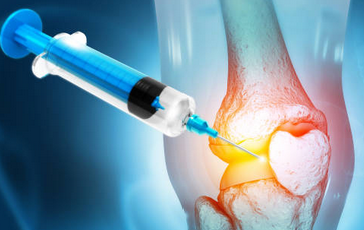

무릎 연골 찢어짐은 진단과 치료가 필요한 질환입니다. 만약 위와 같은 증상이 있다면 의사와 상담하고 적절한 검사와 치료를 받아야 합니다. 치료 방법은 부상의 정도와 위치, 환자의 나이와 건강 상태 등에 따라 다르게 결정될 수 있습니다. 일반적으로는 약물 치료, 물리 치료, 관절 주사 등의 비수술적인 방법으로 치료할 수 있으며, 경우에 따라서는 수술이 필요할 수도 있습니다.

무릎 연골 찢어짐의 치료방법은 손상의 정도와 위치에 따라 다르지만, 일반적으로는 약물 치료, 물리 치료, 수술 치료 등이 있습니다. 약물 치료는 통증과 염증을 줄여주는 약을 복용하는 방법입니다. 물리 치료는 무릎 관절의 움직임과 근력을 회복하기 위해 운동이나 전기 자극 등을 하는 방법입니다. 수술 치료는 손상된 연골을 절제하거나 이식하는 방법입니다.